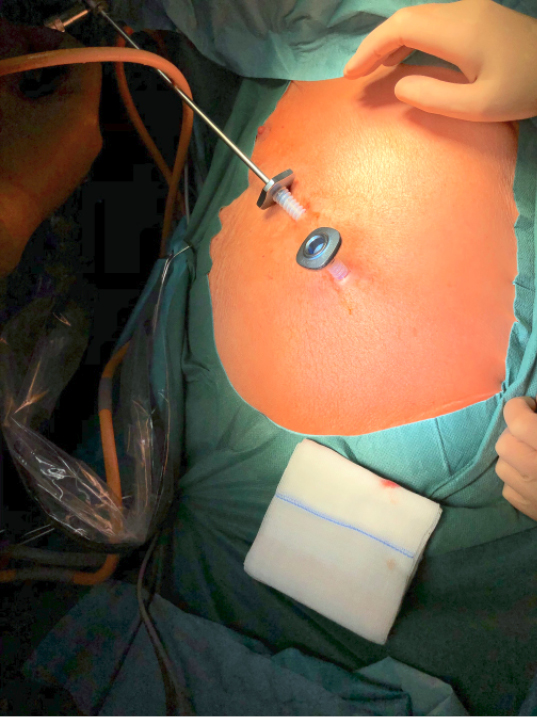

Reduktion des Zugangstraumas –zwei Trokare im selben Interkostalraum –5 mm-Kamera und -Trokare (Abbildung 4) –Kombinationstrokare für Kamera und ein Instrument –Uniportale Operation, bei der Kamera und Instrument über eine einzige nur etwa 3 cm lange Minithorakotomie gesetzt werden |

Abb. 4: Die Verwendung von nur zwei 5-mm-Trokaren und entsprechend einer 5-mm-Kamera minimiert den postoperativen Schmerz.